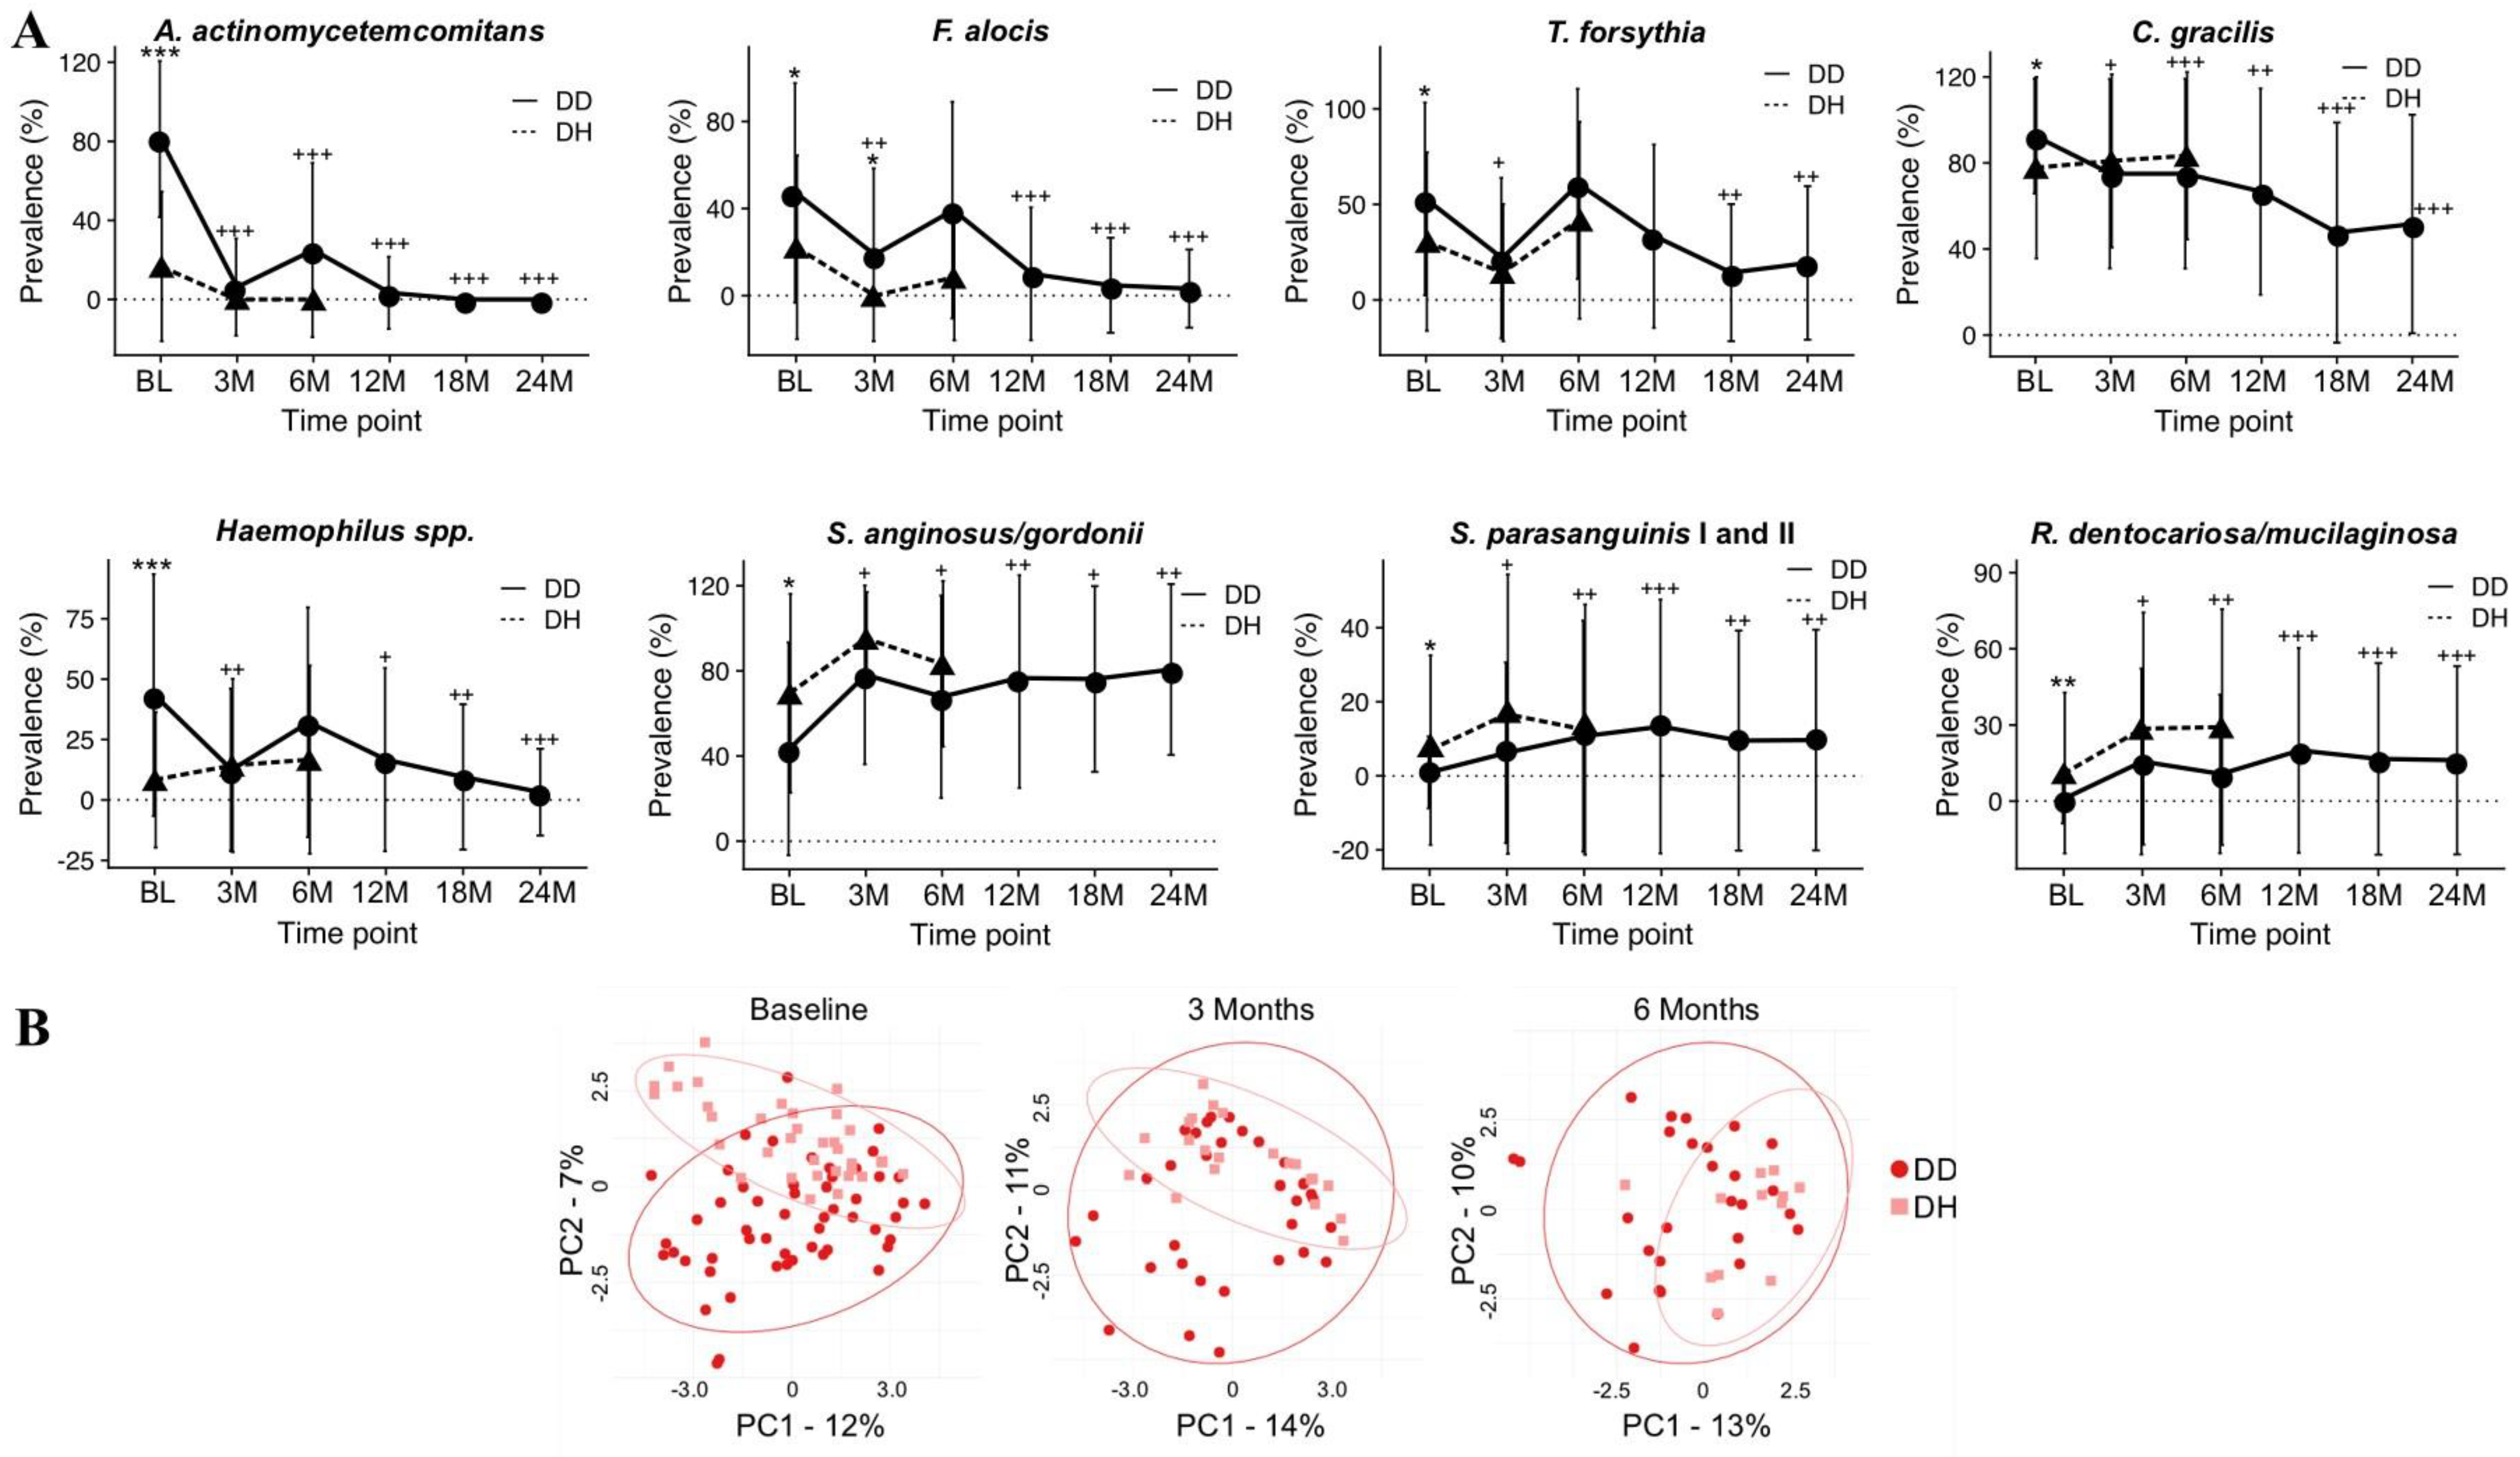

- Velsko, I.M.; Harrison, P.; Chalmers, N.; Barb, J.; Huang, H.; Aukhil, I.; Shaddox, L. Grade C Molar-Incisor Pattern Periodontitis Subgingival Microbial Profile before and after Treatment. J. Oral Microbiol. 2020, 12, 1814674. [Google Scholar] [CrossRef] [PubMed]

- Branco-de-Almeida, L.S.; Velsko, I.M.; de Oliveira, I.C.V.; de Oliveira, R.C.G.; Shaddox, L.M. Impact of Treatment on Host Responses in Young Individuals with Periodontitis. J. Dent. Res. 2023, 102, 473–488. [Google Scholar] [CrossRef]